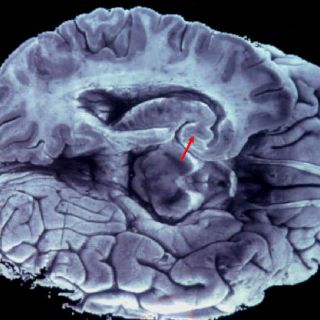

El jefe del Laboratorio de Neurociencias de la Facultad de Psicología de la Universidad Nacional Autónoma de México (UNAM) explicó que el cerebro está dividido en dos hemisferios y para actuar en común se conectan mediante fibras nerviosas, que de llegarse a desconectar es como si el cuerpo estuviera ocupado por dos individuos.

Señaló que existen casos de personas que nacen sin las fibras nerviosas, también llamadas cuerpo calloso, y otros donde se ha tenido que cortar ese filamento por alguna enfermedad.